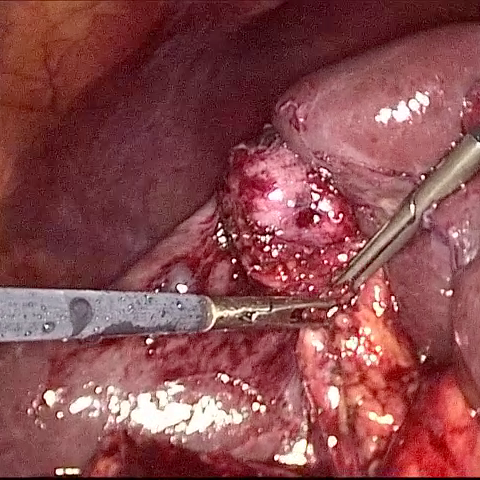

Refer to caption (a) Input Refer to caption (b) case1 Refer to caption (c) case2 Refer to caption (d) case3 Refer to caption (e) Ours Refer to caption (f) Target

Figure 4: Ablation comparisons sampled from the DesmokeData and LSD3K datasets. The first two rows are from DesmokeData and the last two rows are from LSD3K. (settings: case1 = ADA+CrossGating, case2 = DHA+CrossGating, case3 = DHA+ADA).

IV-D Ablation Studies

To validate the effectiveness and individual contributions of the core components of our proposed RGA-Net, we conducted a series of ablation experiments on the DesmokeData dataset. We systematically analyzed the impact of our key designs: the DHA module, the ADA module, and the Cross-Gating (CG) mechanism for feature fusion. In these studies, we created several variants of our network by removing or replacing one component at a time and evaluated their performance. The quantitative results of these experiments are presented in Table II, and qualitative visual comparisons are shown in Fig. 4.

IV-D1 Effectiveness of the Dual-Stream Hybrid Attention Module

The DHA module is designed to capture both local surgical details and global illumination changes by combining shifted window attention with a frequency-domain processing branch. To ablate its effect, we replaced the DHA modules in the encoder with standard Swin Transformer blocks, thus removing the spectral pathway and the hybrid attention mechanism. As demonstrated in Table II, this variant experienced a significant drop in performance. This decline highlights the importance of integrating frequency-domain information, which is crucial for handling the complex light scattering caused by surgical smoke and restoring high-frequency textural details. The results confirm that the dual-stream approach provides a richer feature representation than spatial attention alone.

IV-D2 Effectiveness of the Axis-Decomposed Attention Module

We then investigated the contribution of the ADA module, which is employed in the decoder and latent space to efficiently process multi-scale features. We created a variant where the ADA modules were substituted with a more conventional self-attention mechanism without the block and grid axis decomposition. The results in Table II show a clear degradation in performance for this variant compared to the full model. This outcome validates that factorizing attention along two distinct axes allows the model to capture both fine-grained local patterns and long-range spatial dependencies more effectively and efficiently. The ADA module’s design provides a powerful yet computationally manageable way to model complex feature relationships during the reconstruction phase.

IV-D3 Effectiveness of the Cross-Gating Mechanism

Finally, we analyzed the efficacy of the cross-gating mechanism used for multi-scale feature fusion between the encoder and decoder. We replaced our CG blocks with a standard skip-connection method, specifically simple concatenation followed by a convolutional layer, as is common in many U-Net-based architectures. As shown in Table II, this change resulted in a substantial performance decrease. This finding underscores the superiority of the bidirectional feature modulation offered by our CG mechanism. Unlike simple fusion, cross-gating allows the encoder and decoder pathways to selectively amplify relevant features and suppress irrelevant information from each other, leading to a more refined and effective integration of multi-scale context, which is vital for high-quality image reconstruction.

In conclusion, the ablation studies comprehensively demonstrate that each of our proposed components—DHA, ADA, and CG—is integral to the overall performance of RGA-Net. The full model consistently outperforms all ablated variants, proving the synergistic benefits of our architectural design for the challenging task of surgical smoke removal.